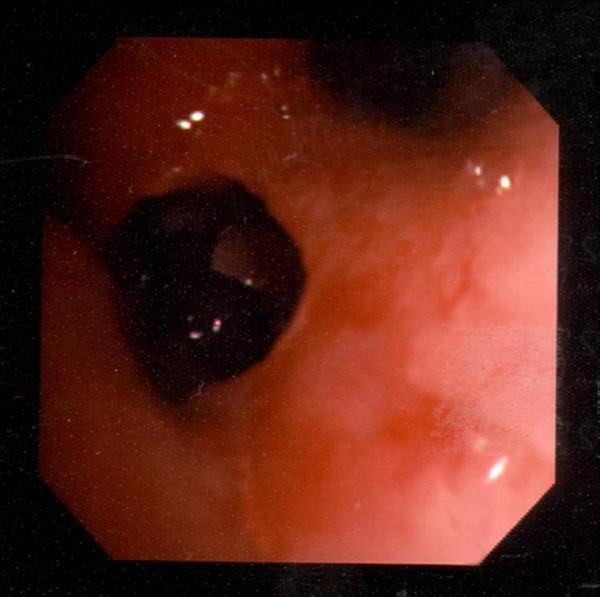

A non-smoking 77-year old gentleman of Indian origin was admitted with a 4-month history of intermittent night sweats, haemoptysis and 6 kg of weight loss. CT scan of thorax demonstrated a 2.5 cm mass in the right middle lobe with multiple small nodules within the right lung and confirmed the presence of mediastinal and hilar lymph nodes.Fibreoptic bronchoscopy demonstrated a distorted right main bronchus, anterior shift of the right upper lobe and occlusion of the right middle lobe bronchus with a black necrotic ulcer. Mycobacterium tuberculosis was found in the bronchoalveolar lavage and histology demonstrated numerous fungal hyphae with a morphological appearance of zygomycetes within necrotic areas of tissue. Medical management with anti-fungal and anti-mycobacterial treatment was instigated as the patient's pre-existing IHD did not permit surgical intervention. Subsequently CT imaging following completion of therapy demonstrated improvement of the mass and a resolution of the associated nodules. The patient has been followed for 6 months to date and there has been no recurrence of symptoms. Recent bronchoalveolar lavage cultures have been negative for M. tuberculosis and zygomycetes.

一位77岁、非裔印度裔的不吸烟男性因间歇性盗汗、咯血和体重减轻6公斤,持续4个月而入院。胸部CT扫描显示右中叶有一个2.5厘米的肿块,右肺内有多个小结节,并证实存在纵隔和肺门淋巴结。纤维支气管镜检查显示右主支气管变形,右上叶向前移位,右中叶支气管被黑色坏死性溃疡阻塞。支气管肺泡灌洗中发现结核分枝杆菌,组织学检查显示在组织坏死区域有大量形态为接合菌的真菌菌丝。由于患者先前存在的缺血性心脏病不允许进行手术干预,因此开始进行抗真菌和抗分枝杆菌治疗。治疗完成后的CT成像显示肿块有所改善,相关结节消退。该患者至今已随访6个月,症状未复发。最近的支气管肺泡灌洗培养对结核分枝杆菌和接合菌均为阴性。